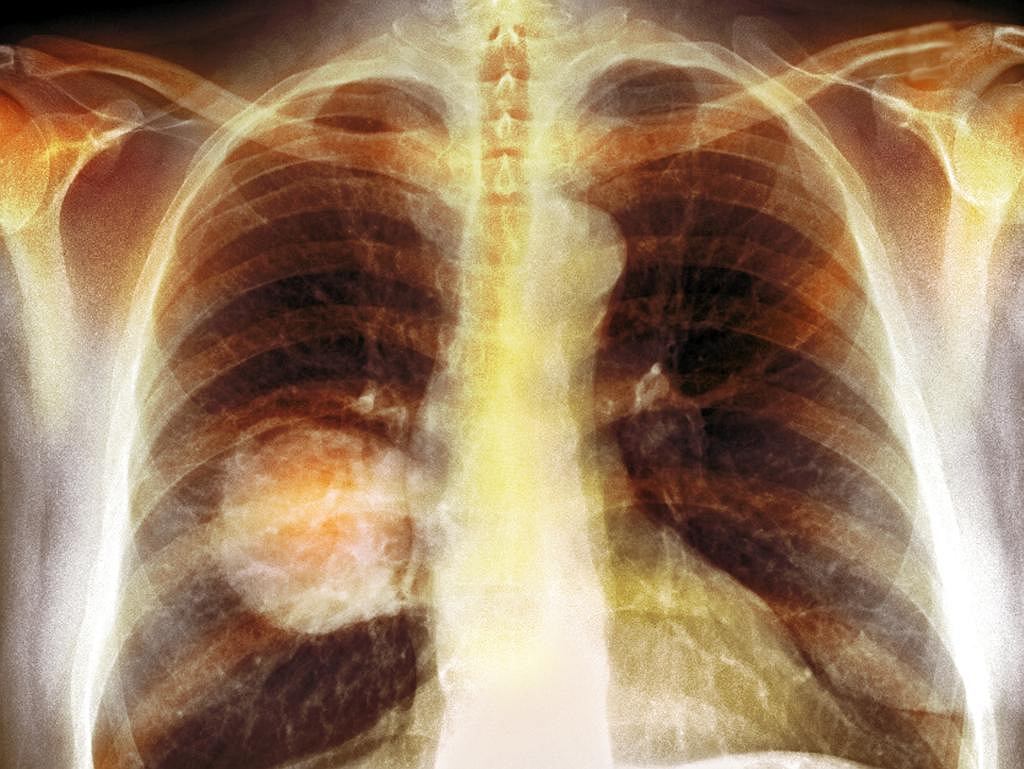

RAK PŁUC

Rokowania dla chorych na raka płuc są bardzo złe. Osoby, które nie są leczone, umrą prawdopodobnie za rok lub trochę później, niezależnie od rodzaju nowotworu. W ostatnim roku życia może dojść do bardzo nieprzyjemnych objawów, takich jak krwioplucie i utrata tchu. Zadziwiająco dużo palaczy uważa, że skoro palenie tytoniu zabija, to i tak jest dla nich za późno na zaniechanie palenia. To nieprawda. Rzucenie palenia naprawdę pomaga. Oczywiście, jeżeli będziesz czekał, aż zachorujesz na raka płuc, to będzie rzeczywiście za późno, ale jeżeli rzucisz palenie, zanim zaatakuje cię poważna choroba, znacznie zmniejszysz ryzyko śmierci z powodu palenia.